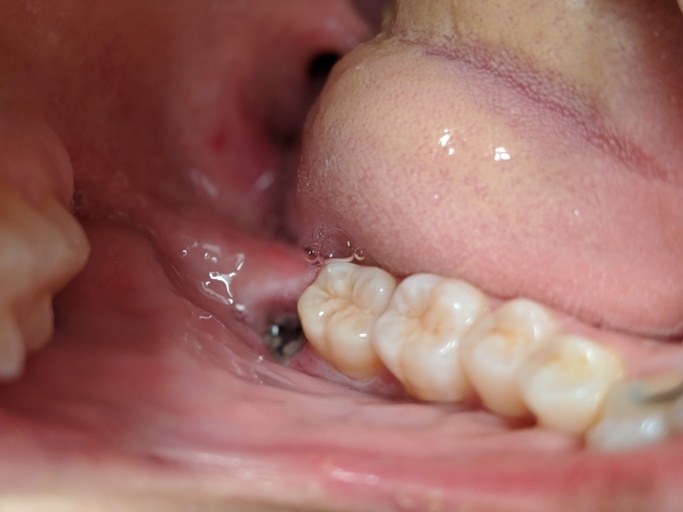

Is my widom Tooth Socket healing normally?

It's day 2 post surgery and I'm noticing grey inside my socket. Is it healing normally? Pain is not too bad although I'm taking ibuprofen every six hours. I'm using salt water rinses after ever meal. I want to be sure I don't have dry socket. I'm eating soft foods, not using the syringe yet. How long does it take to heal completely?